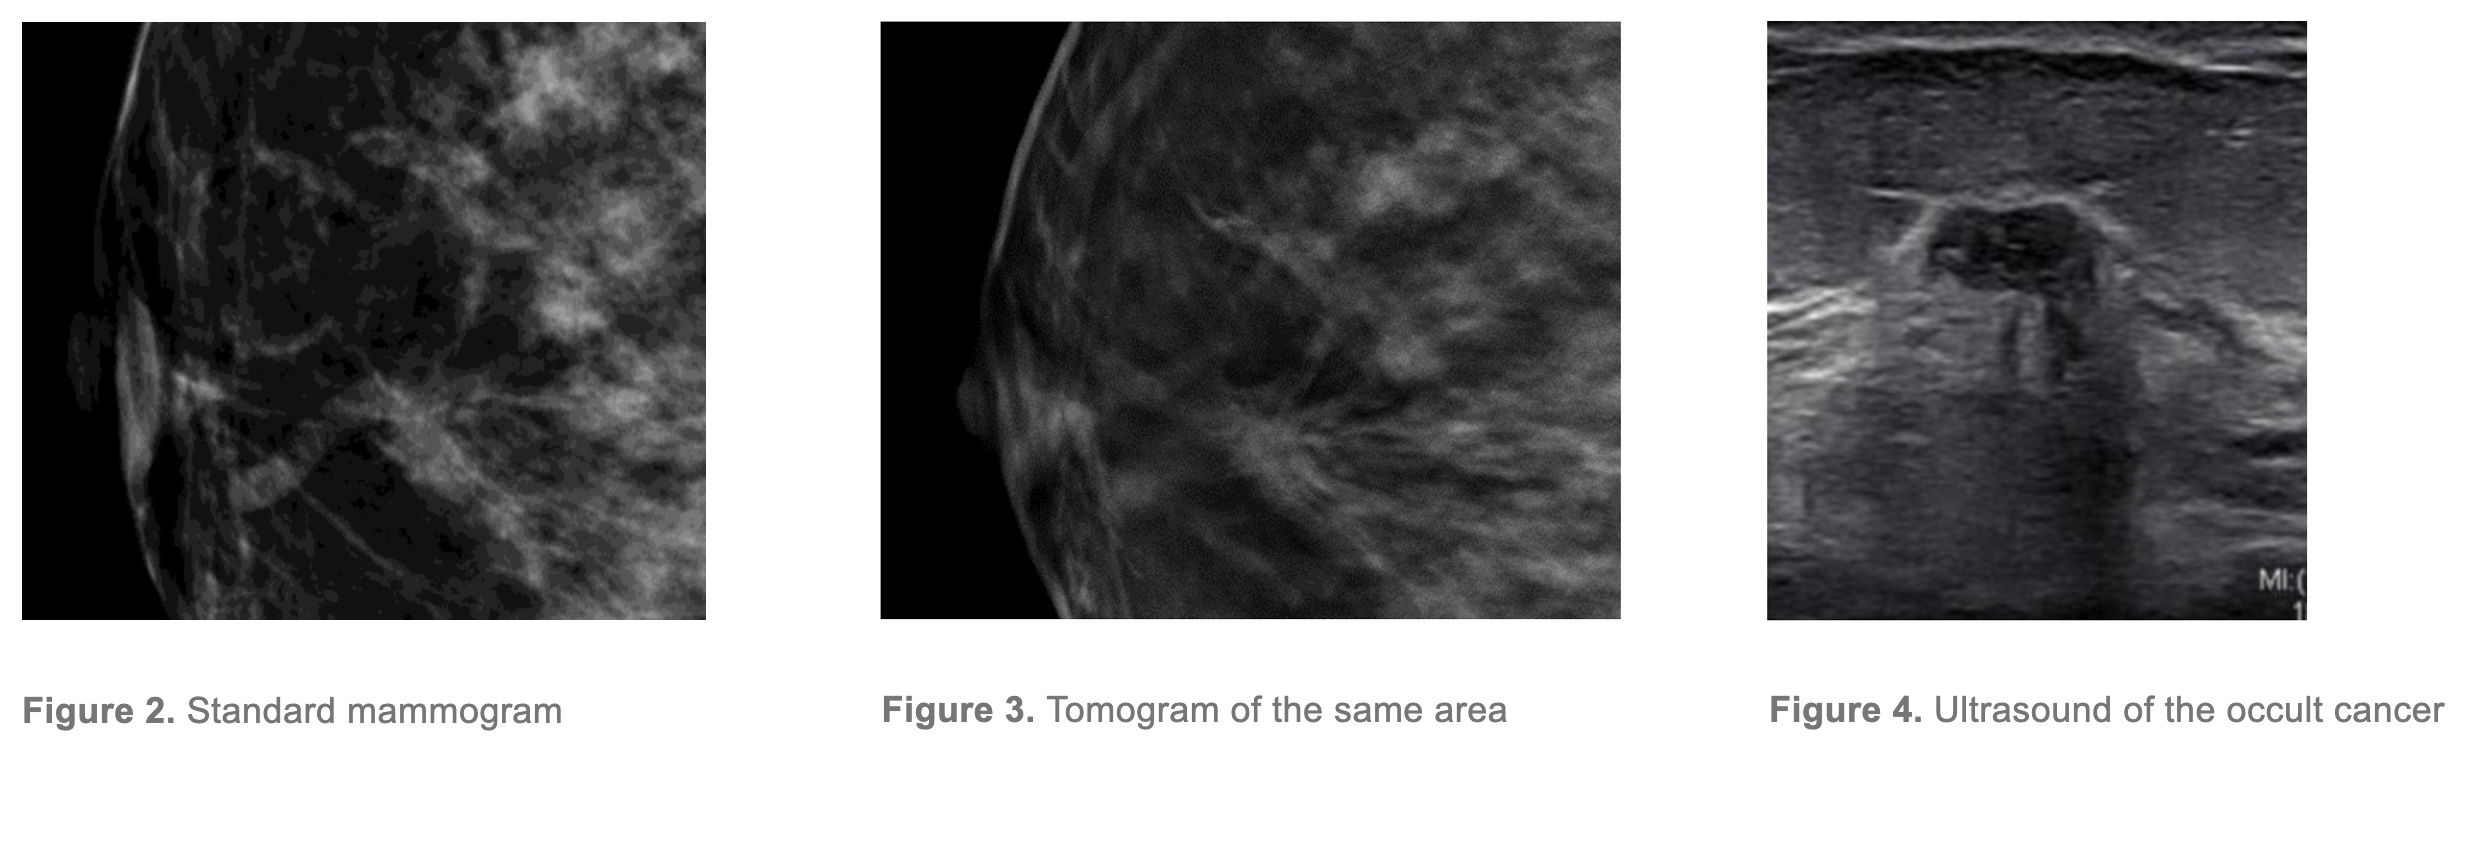

3D mammography (Digital Tomosynthesis) has approximately 25% better overall cancer detection rate than 2D (standard) mammography3

At Sydney Breast Clinic, we aim to optimise cancer detection by using the latest digital mammogram technology. Digital breast tomosynthesis, often called 3D mammography, is used for all women having a mammogram. DBT uses a series of angled images reconstructed into slices. This improves cancer detection (sensitivity) and confirms normal findings when superimposed normal breast tissue mimics an abnormality (specificity).

Ultrasound in addition to mammography will improve detection of asymptomatic cancer by up to 50%4

We use the mammographic density to guide the use of ultrasound examination. All women with category C or D mammographic density will be recommended a bilateral ultrasound examination following their mammogram and clinical examination, even if they are asymptomatic, and even if the tomogram showed no signs of malignancy. This is because we know that significant lesions may be obscured on mammography by general breast tissue density.